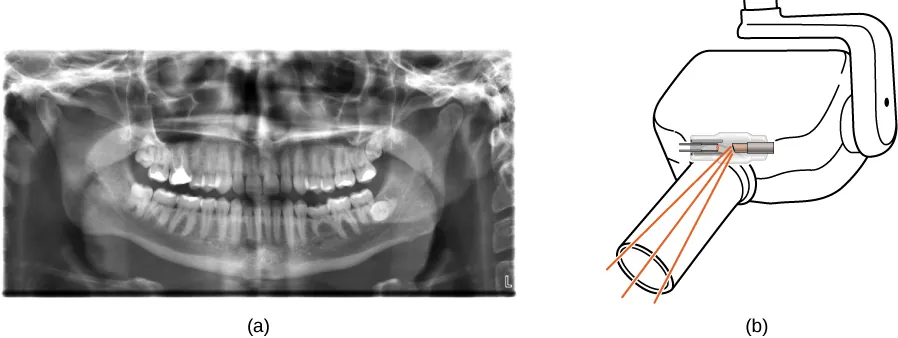

La figura (a) muestra una imagen radiográfica de la vista frontal de la mandíbula, especialmente de los dientes. La figura (b) muestra un dibujo de una máquina de rayos X dental.

Figura 8.25 (a) Una imagen de rayos X de los dientes de una persona. (b) Una máquina de rayos X típica en la consulta de un dentista produce una radiación de energía relativamente baja para minimizar la exposición del paciente (crédito: modificación de la obra de "Dmitry G"/Wikimedia Commons).